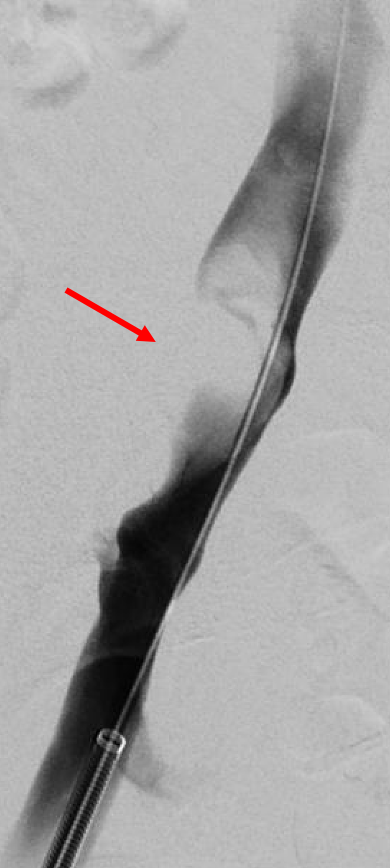

During consultation, we discuss that we should proceed with venography to characterize the nature of this lesion. Venography is performed, demonstrating a filling defect in the right external iliac vein (Figure 2, red arrow). However, it does not have the appearance of thrombus, as it appears eccentric, almost wall-attached.